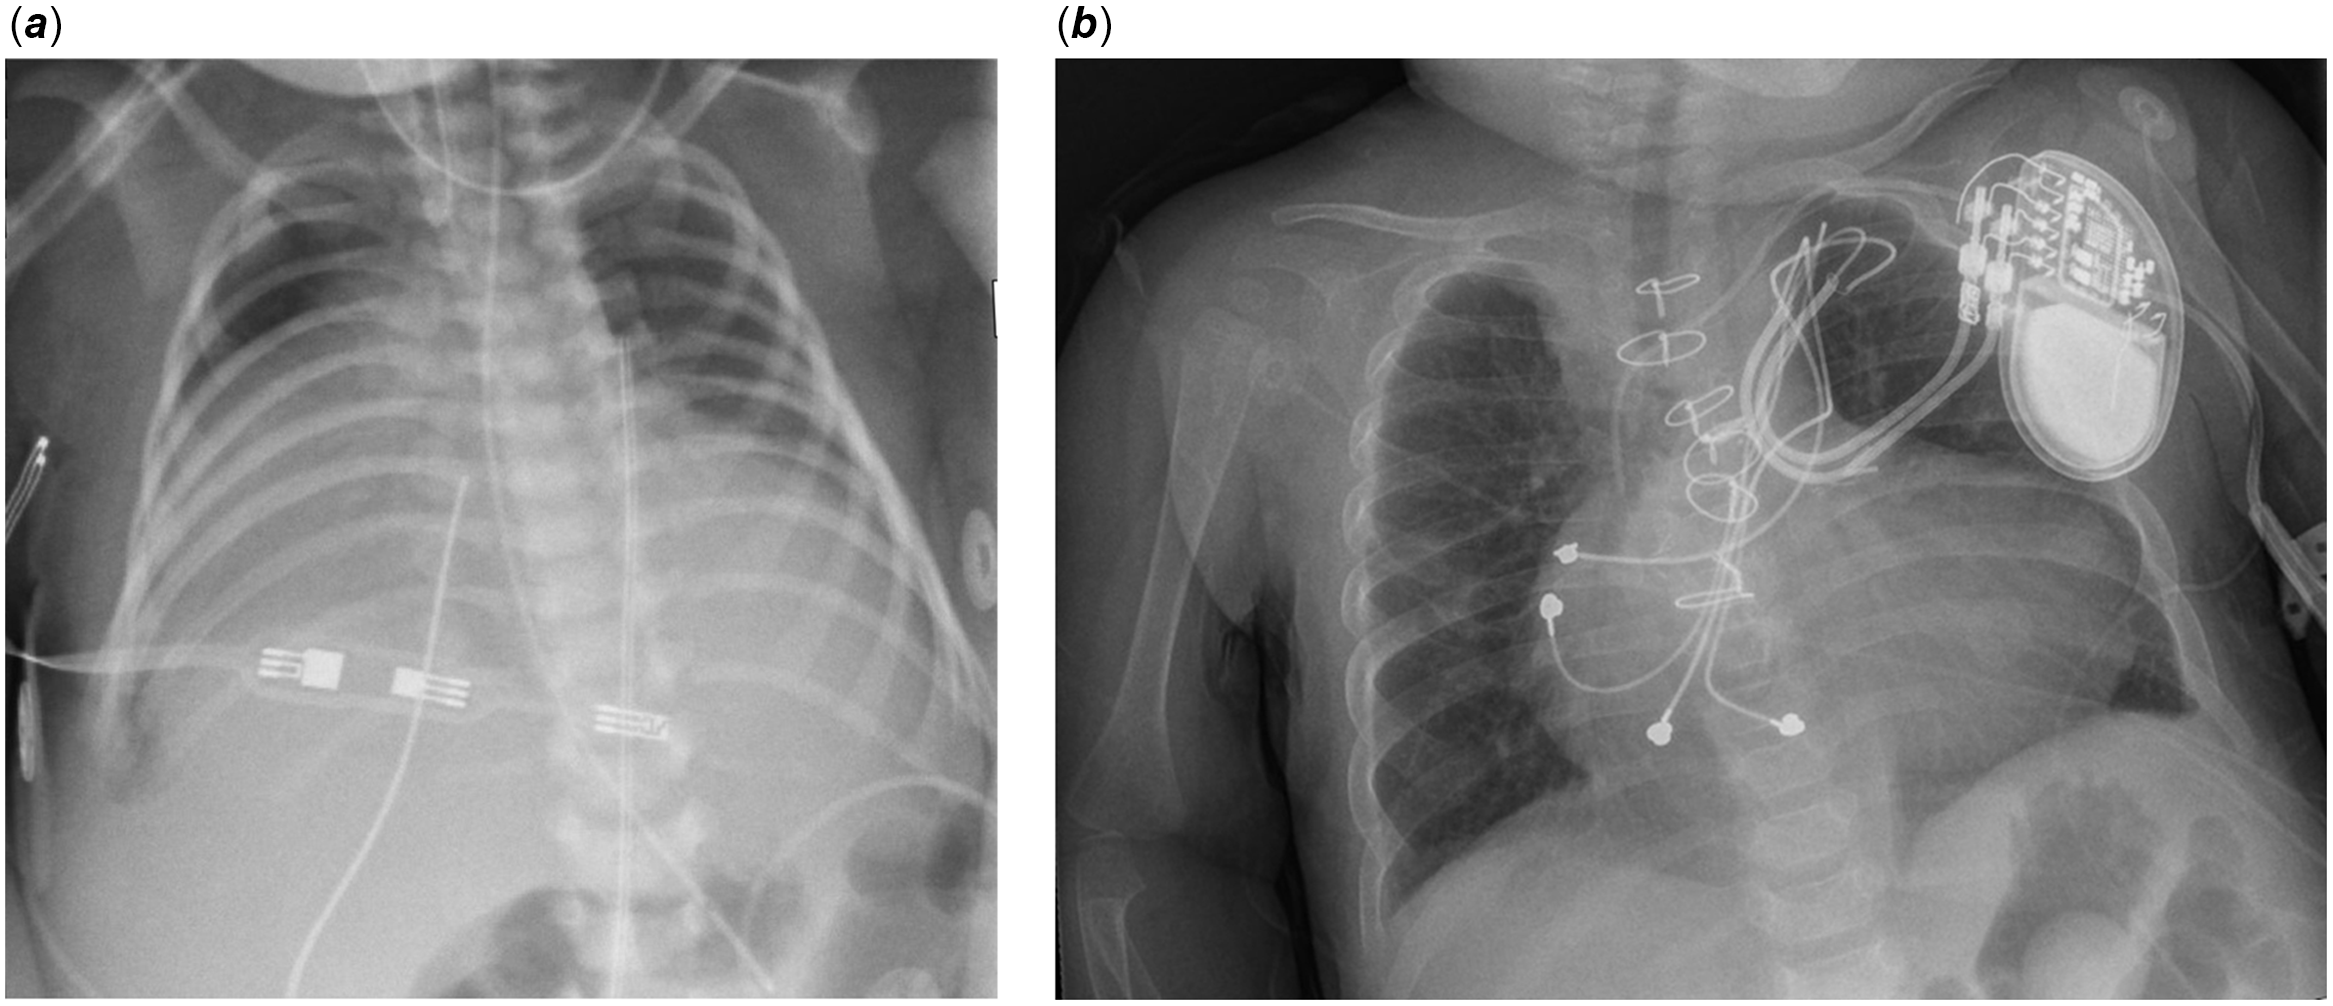

The patient was prenatally diagnosed with severe Ebstein’s anomaly and developed hydrops fetalis during the third trimester. She was delivered at 36 weeks gestation via emergent Caesarean section due to supraventricular tachycardia and fetal distress. Birthweight was 2.68 kilograms with an APGAR score of 6 at 1 minute of life. She was intubated at 4 minutes of life due to hypoxia. Post-natal echocardiography confirmed a Great Ormond Street Echocardiography score 1.16 (Grade 3), Carpentier type C Ebstein’s anomaly with massive right atrial dilation, anatomic pulmonary atresia, and apically displaced tricuspid valve with severe regurgitation (Fig. 1a). Chest X-ray demonstrated a cardiothoracic ratio of 1.0 (Fig. 2a). The patient remained paralysed on invasive positive pressure mechanical ventilation with prostaglandin infusion. She underwent Starnes procedure on day of life 4 with fenestrated Goretex patch right ventricular exclusion, right atrial reduction plasty, ductal ligation, and 3-millimetre central aortopulmonary shunt. She required central post-cardiotomy extracorporeal membrane oxygenator support, with decannulation and sternal closure on postoperative day 4.

Figure 2. a : Chest X-ray day on of life 2, cardiothoracic ratio 1.0. b : Chest X-ray at 11 months of age, cardiothoracic ratio 0.66.

In consideration of her shunt-dependent physiology and the extensive hepatectomy required, neoadjuvant chemotherapy with cisplatin was selected for local disease control. Despite adequate hyperhydration, this regimen resulted in acute kidney injury and severe immunosuppression with Candida parapsilosis fungemia, sepsis, and multi-drug resistant pneumonias. These complications delayed subsequent chemotherapy until 5 months of age, when she received three cycles of vincristine and irinotecan. At 8 months of age, she underwent bidirectional cavopulmonary shunt (Glenn procedure) with pacemaker generator relocation to the left deltopectoral region. She developed early stenosis of the cavopulmonary anastomosis with nonocclusive thrombus, requiring thrombectomy and patch plasty 3 weeks postoperatively. Subsequently, her respiratory and renal insufficiency improved dramatically. By 11 months of age, her Great Ormond Street Echocardiography score decreased to 0.4 (Grade 1, Fig. 1b) and cardiothoracic ratio to 0.66 (Fig. 2b). She maintained appropriate local control of her hepatoblastoma, as evidenced by sequential imaging and alpha-fetoprotein levels, and then underwent radiofrequency ablation at an outside institution in lieu of hepatectomy. She remained stable from a cardiorespiratory standpoint and was discharged home on postoperative day 344. She received four additional cycles of outpatient cisplatin and currently remains in remission.